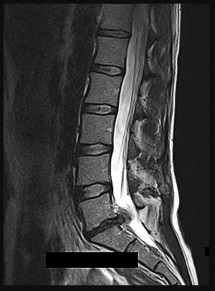

A 32-year-old male is involved in a high-speed motor vehicle collision and arrives with a unilateral C6-C7 facet dislocation and a dense C6 radiculopathy. Closed reduction with cranial tongs is attempted in the awake patient but is unsuccessful. What is the most appropriate next step in management?

- Obtain an urgent MRI of the cervical spine followed by surgical intervention

Correct Answer: Obtain an urgent MRI of the cervical spine followed by surgical intervention

Explanation:

In cases of cervical facet dislocation where awake closed reduction fails, or in a patient who cannot be examined (e.g., obtunded), an MRI of the cervical spine is the standard of care before proceeding to open reduction. The MRI is essential to identify the presence of a herniated intervertebral disc. If an anterior disc herniation is present, a posterior-only open reduction poses a significant risk of extruding the disc further into the spinal canal, potentially causing a catastrophic spinal cord injury. Therefore, MRI dictates whether an anterior approach (to remove the disc before reduction) is required.